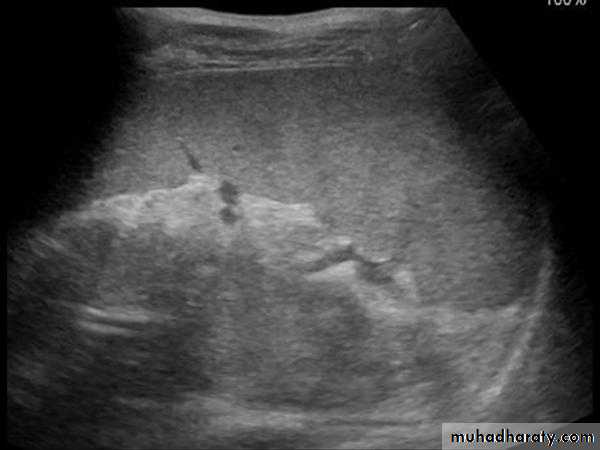

Focal masses ultrasound

Multiple masses